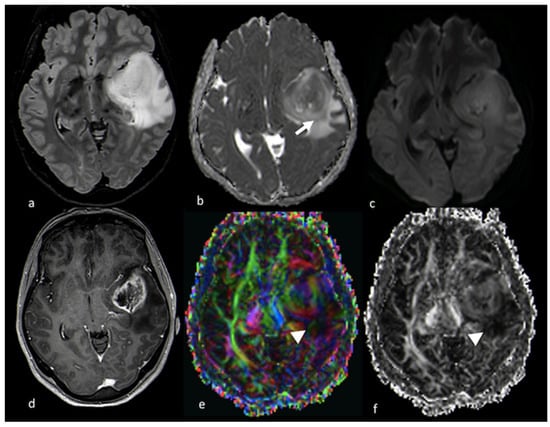

3.2. Diffusion Imaging Techniques

3.2.2. Diffusion Tensor Imaging (DTI)

- Sternberg, E.J.; Lipton, M.L.; Burns, J. Utility of diffusion tensor imaging in evaluation of the peritumoral region in patients with primary and metastatic brain tumors. AJNR Am. J. Neuroradiol. 2014, 35, 439–444. [Google Scholar] [CrossRef]

- Wang, S.; Kim, S.; Chawla, S.; Wolf, R.L.; Knipp, D.E.; Vossough, A.; O’Rourke, D.M.; Judy, K.D.; Poptani, H.; Melhem, E.R. Differentiation between Glioblastomas, Solitary Brain Metastases, and Primary Cerebral Lymphomas Using Diffusion Tensor and Dynamic Susceptibility Contrast-Enhanced MR Imaging. Am. J. Neuroradiol. 2011, 32, 507–514. [Google Scholar] [CrossRef] [PubMed]